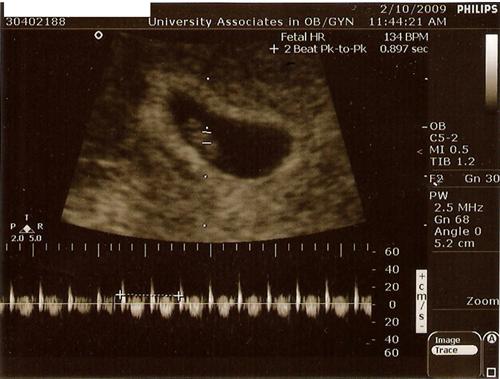

I went for my 1st sono today. We got to see and hear the heartbeat. It was so cool! I was so worried but the tech said everything looks great. I didn't even have to do an internal.

Here's our little blueberry:

7wk 2days